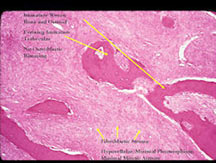

Microscopic Pathology

- Parosteal osteosarcoma is a low grade, well differentiated fibroblastic tumor that produces bone/osteoid (immature woven bone). It arises from the surface of the bone, namely the outer layer of the periosteum. It is slow growing and slow to metastasize.

- Usually a low grade tumor with fibroblastic stroma and osteoid/woven bone